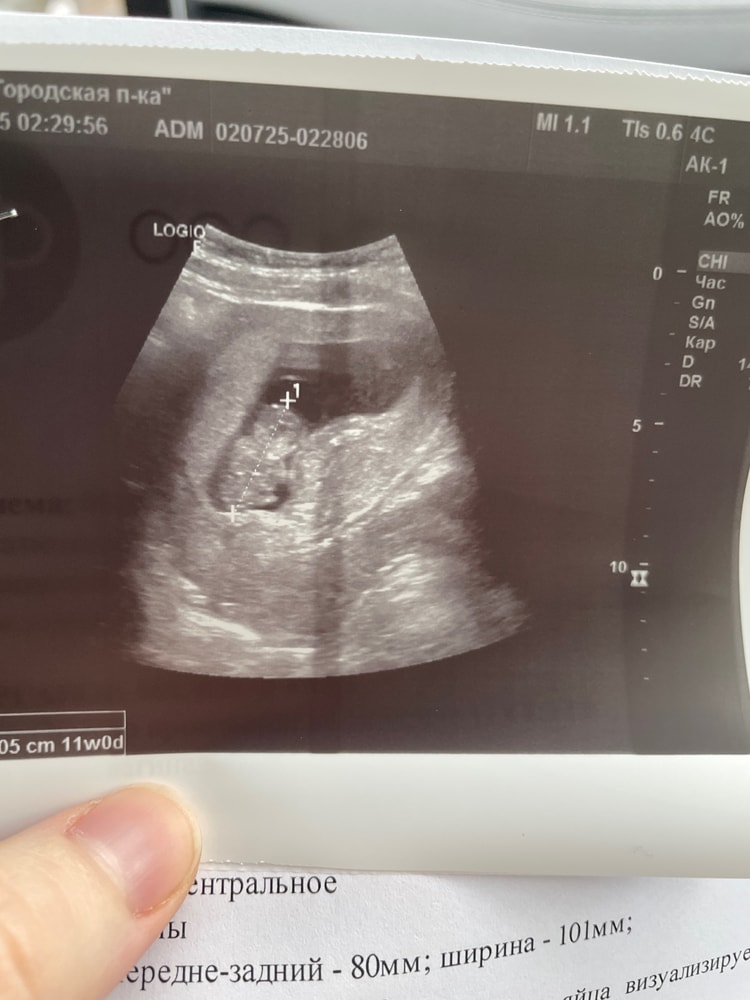

1.07 ходили с мужем в платную клинику , слушали сердечко,малыш лежал к нам спинкой.

А уже 8.07.25г на узи мне подтвердили, что не бьется сердечко ♥️

пришла, что бы продлили мне больничный. Врач сказала «пошли послушаем сердечко», я сразу поняла по ее лицу все .. она меня повела на другой аппарат к другому узисту. Та сразу сказала, что плод замер, показала мне на экране 🥲так и лежал спинкой. Срок на тот момент у меня был 12 недель и 4 дня ( по менструации) , плод отставал от этого срока.

оставлю здесь на память ❤️что ты был со мной , хоть и так мало